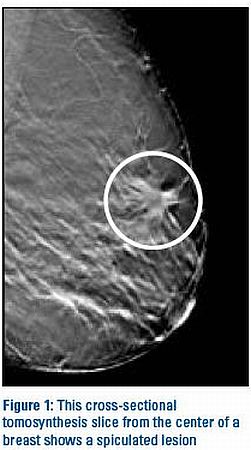

A tomossíntese*, nova técnica de detecção do câncer de mama, será apresentada durante a Jornada Paulista de Radiologia, que acontece entre os dias 29 de abril e 2 de maio, no Transamerica Expo Center**. Trata-se de uma mamografia em 3D que elimina a superposição de tecidos, melhora a visualização dos contornos das lesões e aumenta entre 10% e 15% a detecção da doença, de acordo com estudos iniciais.

Na opinião de Aron Belfer, em termos de tecnologia, a mamografia digital 2D é um avanço importante em relação à mamografia analógica, convencional. Já a tomossíntese, de acordo com estudos recentes, surge como uma tecnologia capaz de detectar lesões que antes passariam despercebidas na mamografia digital 2D. “A detecção de tumores menores permite recorrer a cirurgias menos mutilantes, resulta em menor custo global do tratamento, maior sobrevida e melhor qualidade de vida das pacientes”.